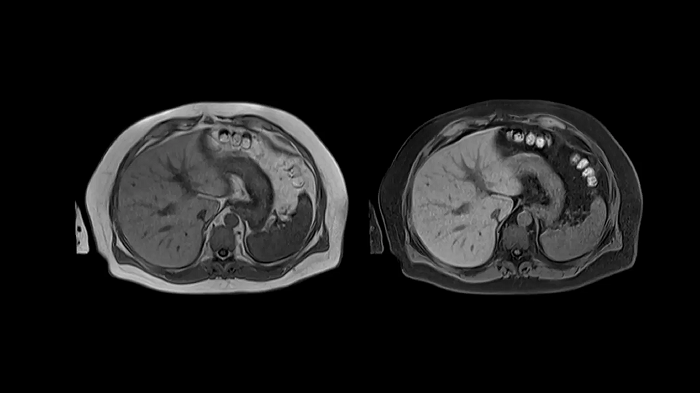

T1 VIBE Dixon with CAIPIRINHA

Benefit from Siemens Healthineers’ dedicated CAIPIRINHA acceleration to gain a complete abdominal volume within a single breath-hold. The Dixon technique offers outstanding fat-water separation for a flawless representation of the abdominal anatomy.

- Contour L Coil

- Spine Coil

Image Courtesy: University Hospital Erlangen, Germany | Image-ID: 4aaaa0458